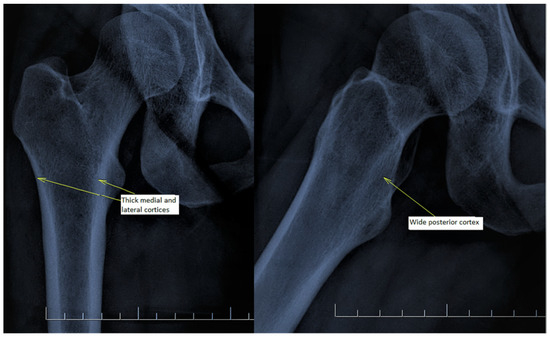

There are also osteoporosis measurements that can be detected by direct radiography, such as the Singh index, Dorr index, cortical thickness index, and canal-to-calcar isthmus ratio. The Singh Index (SI) is a method of measuring osteoporosis determined by detecting trabecular patterns in the proximal femur with plain radiographs. According to the Singh index, osteoporosis is divided into six grades (Grades 1–6). As the grade progresses, the level of osteoporosis decreases; grades 1–3 define definitive osteoporosis (Figure 1) [8]. The Dorr index (DI) is divided into three types according to cortical thickness on proximal femur radiographs (Types A-B-C). As the type progresses, the level of osteoporosis increases (Figure 2) [9,10]. The cortical thickness index (CTI) is measured 10 cm distal to the trochanter minor; its decrease indicates that the cortex is thinning, thus increasing osteoporosis (Figure 3) [9,10]. The canal-to-calcar isthmus ratio (CCR) is calculated as the ratio of the canal diameter 10 cm distal to the trochanter minor to the canal diameter at the calcar on plain radiographs. An increase in this ratio indicates an increase in osteoporosis (Figure 4) [9,10].

Figure 3. The cortical thickness index is measured 10 cm distal to the mid-lesser trochanteric line ((X − Y)/X). It is defined as the ratio of the difference between the diameter of the femoral diaphysis (X) and the diameter of the intramedullary canal (Y) to the diameter of the femoral diaphysis. It was measured as 0.58 ((36.3 − 15.3)/36.3) on the X-ray of the patient.